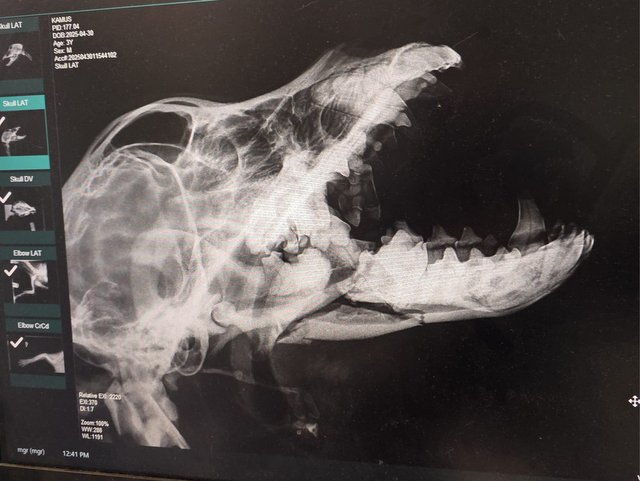

Röntgenbilder zeigten das Ausmaß der Zerstörung des Unterkiefers und den Bruch eines Beines.

Dieser Hund muss grausame Schmerzen haben, Zähne sind aus der Verankerung gerissen und sein Gesichtsschädel ist nicht mehr symmetrisch. Ein großes Stück des Unterkiefers ist komplett abgebrochen.

Nur weil gestern auch in Nordmazedonien ein Feiertag war, musste Camush, das ist jetzt sein Name, noch ausharren. Zwar mit Schmerzmitteln im Blut, einer Sonde im Magen, aber nicht in der Lage sein Maul zu schließen.